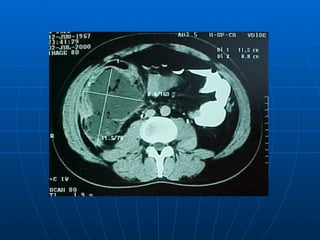

APENDICITIS AGUDA TOMOGRAFIA COMPUTARIZADA : En algunos hospitales se ha valorado el costo beneficio entre practicar una y dejar en observación un día a los casos dudosos o operar demasiado tarde. Tiene un 93-98 % de exactitud diagnóstica sobretodo cuando se usa contraste. Ha disminuido el % de apendicetomías negativas del 20 al 7%  adultos y en pediátricos del 13 a 7%. LAPAROSCOPIA DIAGNÓSTICA Y/0   TERAPEUTICA  más en mujeres en edad fértil.

APENDICITIS AGUDA TOMOGRAFIACOMPUTARIZADA : En algunos hospitales se ha valorado el costo beneficio entre practicar una y dejar en observación un día a los casos dudosos o operar demasiado tarde. Tiene un 93-98 % de exactitud diagnóstica sobretodo cuando se usa contraste. Ha disminuido el % de apendicetomías negativas del 20 al 7% adultos y en pediátricos del 13 a 7%. LAPAROSCOPIA DIAGNÓSTICA Y/0 TERAPEUTICA más en mujeres en edad fértil.